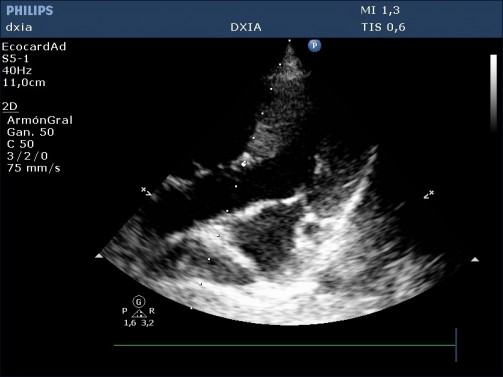

Predominancia de cámaras derecha, con marcada dilatación de estas (AD y VD)

Hipertrofia moderada de pared libre del VD y del SIV

No aplanamiento septal